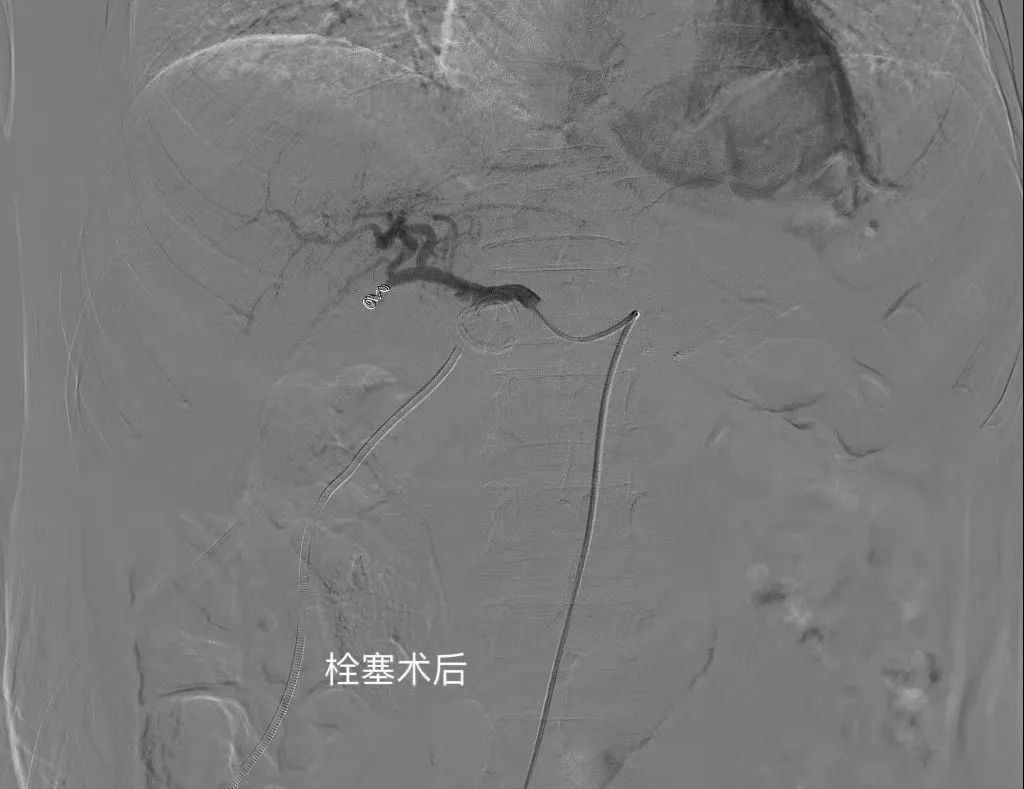

术中通过微导管造影,精准找到刘大爷出血点位于肝动脉,进行精准动脉栓塞止血后,顺利完成微创介入手术。手术过程中,刘大爷体征平稳,术后安全返回病房。

介入栓塞术后精准止血